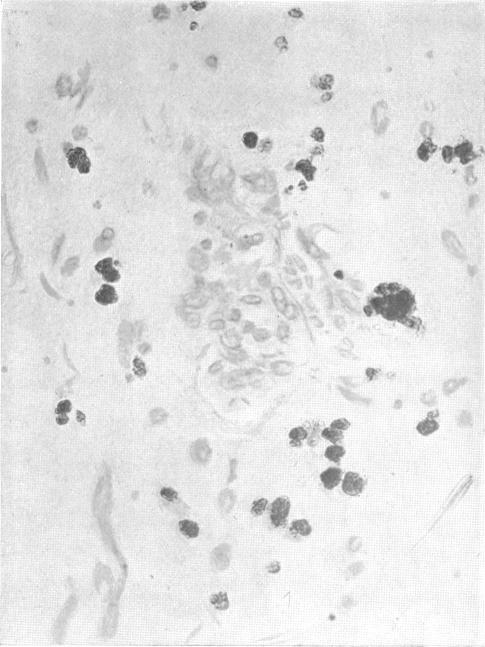

CARDIAC MYXOMA A CLINICAL AND PATHOLOGICAL STUDY.

Br Heart J. 1939 Jul;1(3):249-60. doi: 10.1136/hrt.1.3.249.